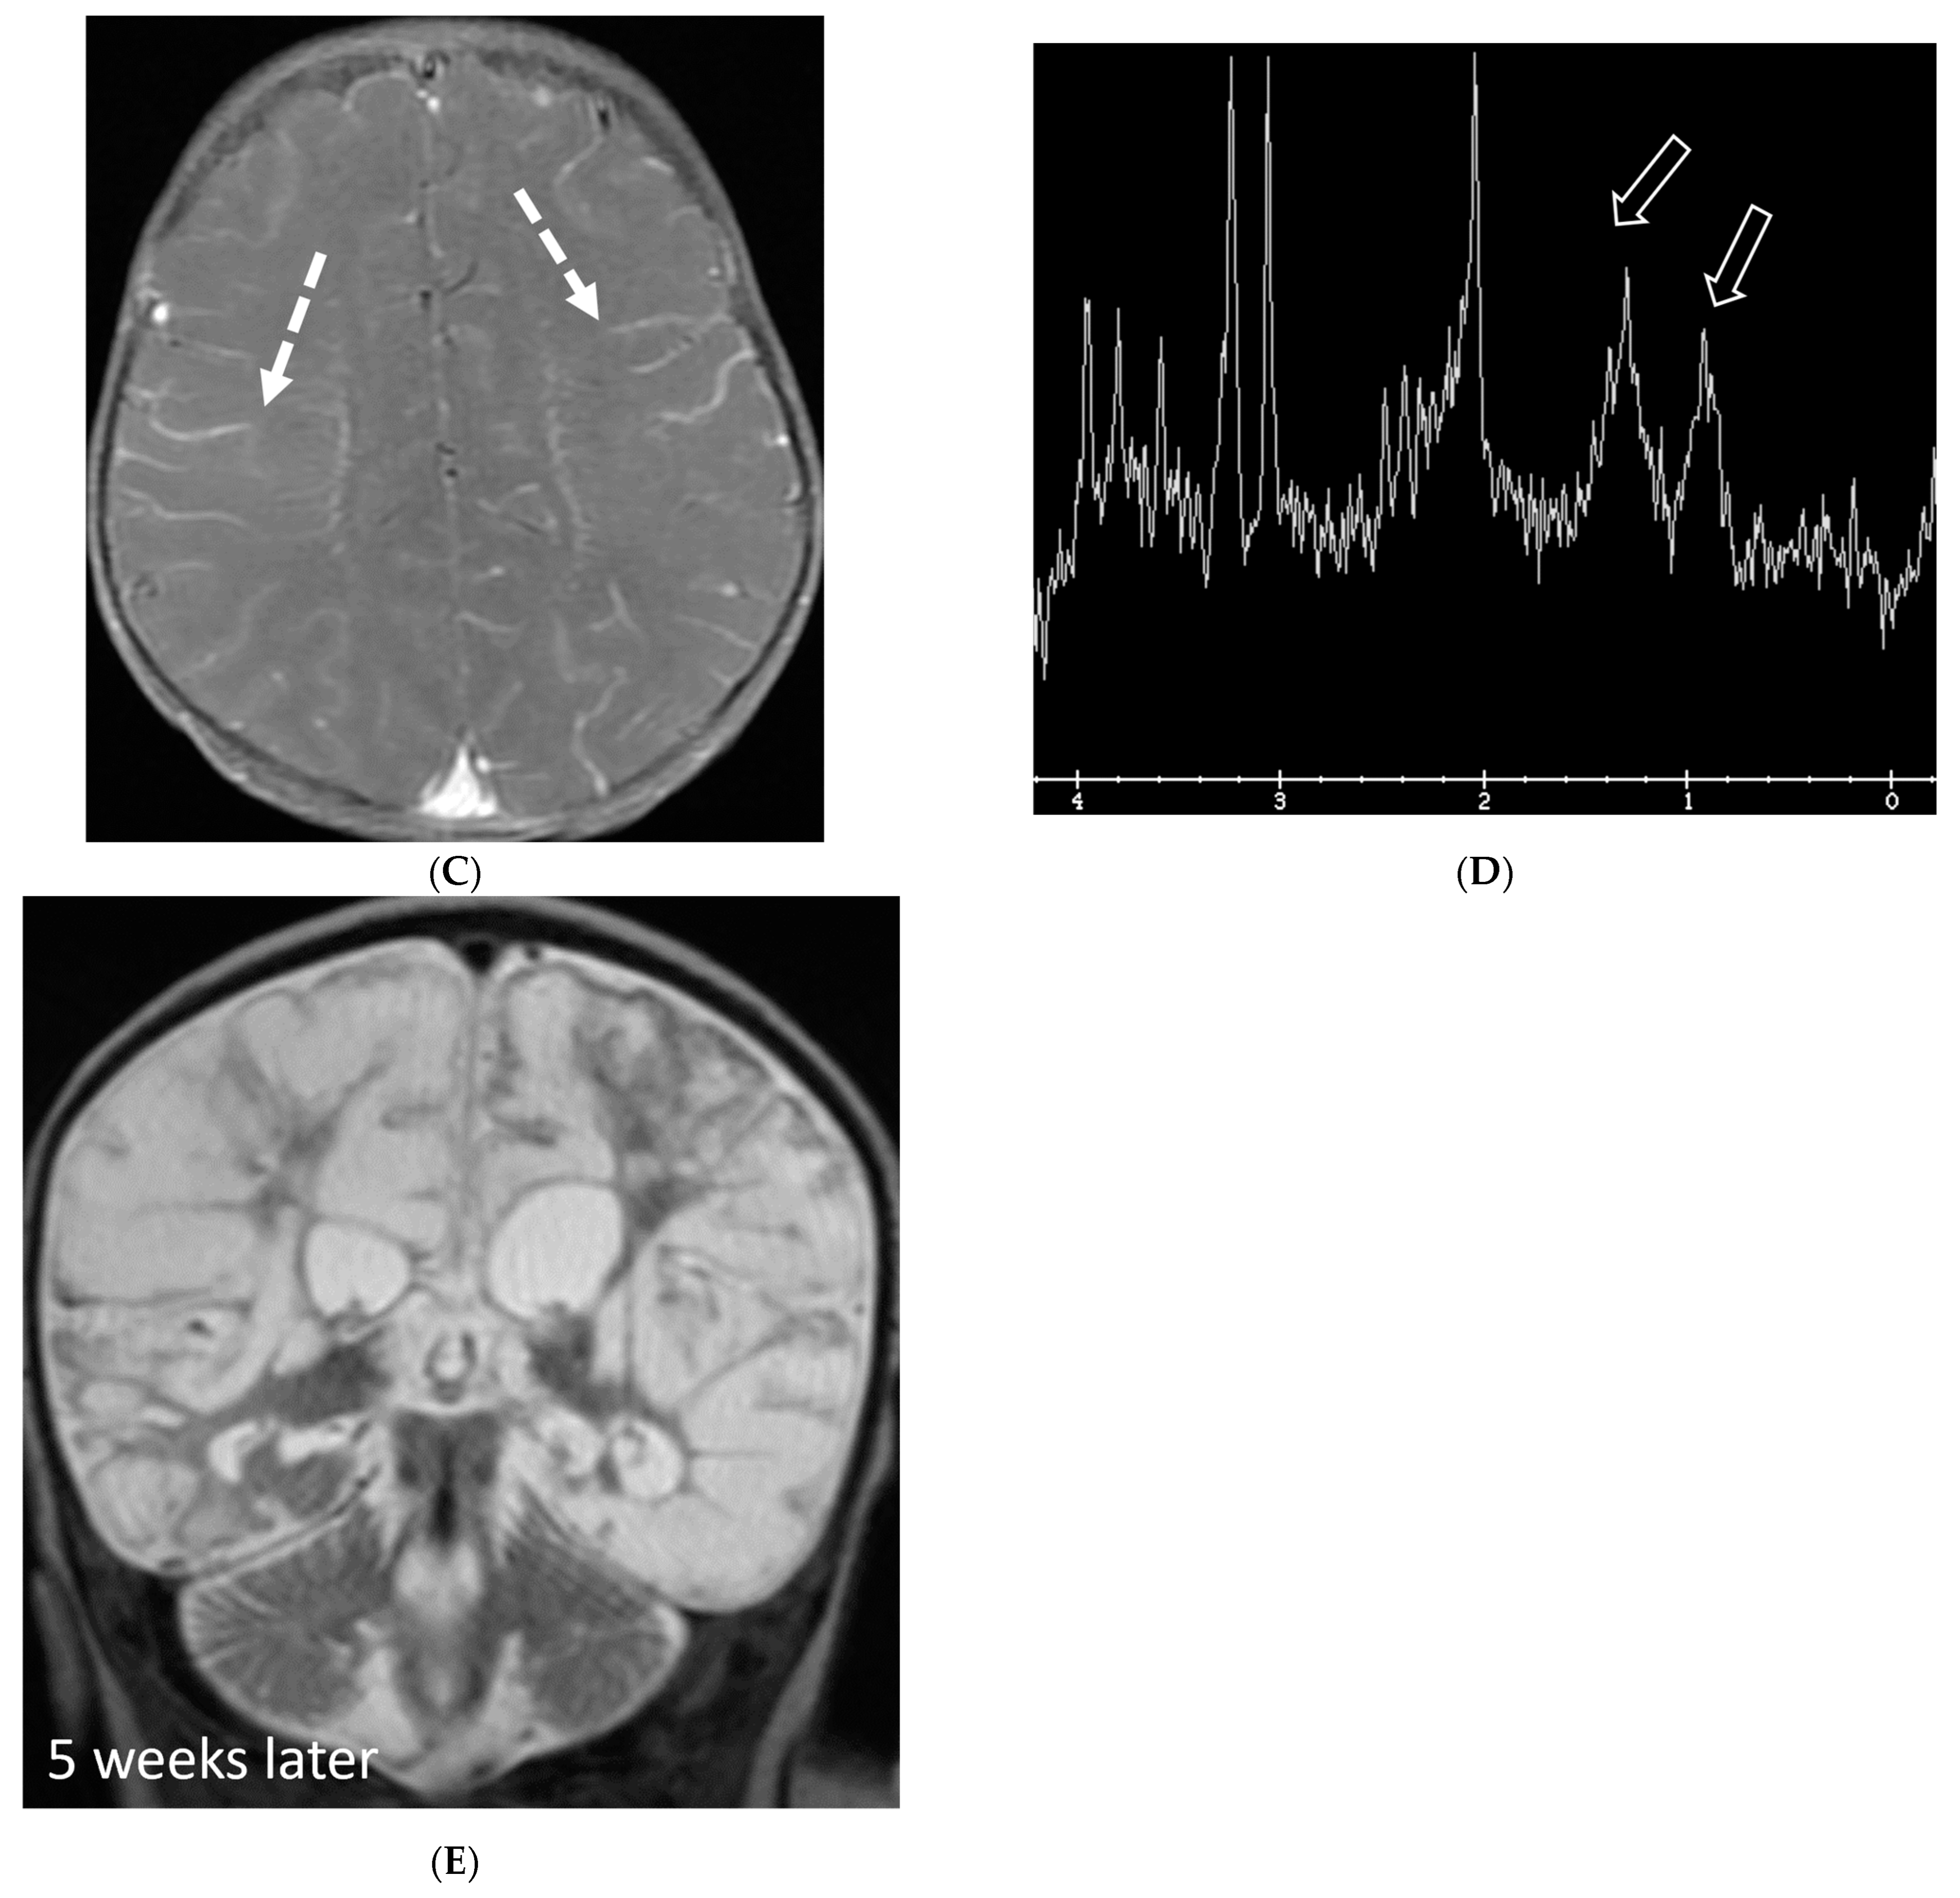

Several viruses, such as enterovirus, herpes simplex virus (HSV)-1&2, mumps, varicella, and arbovirus, can infect children, out of which enterovirus is the most common. These organisms have variable LME, ranging from none to diffuse sulcal LME, best demonstrated on post contrast FLAIR over T1 images [97]. HSV is associated with poor prognosis due to associated parenchymal involvement. HSV-1 commonly causes oral herpes in contrast to HSV-2 which typically causes genital herpes in adults. An active/remote HSV 2 infection in the mother increases the risk of neonatal transmission if delivered vaginally.

HSV 2 typically causes diffuse cortical involvement with diffusion restriction, loss of gray white matter differentiation and basal ganglia involvement in early stages [98]. HSV 1 typically occurs in older children and adolescents and leads to asymmetric temporal lobe involvement with relative sparing of the basal ganglia (Figure 19).

Figure 19.

17-day-old girl with seizures. Axial T2 (A), axial DWI (B), axial T1 post contrast (C), short TE spectroscopy (D) and coronal T2 (E): There is loss of gray white matter differentiation indicating edema in bilateral frontal lobes (arrows). Extensive ischemic changes involving bilateral frontal, bilateral parietal lobes, bilateral perisylvian regions, bilateral thalami (curved arrows). Extensive LME is identified in the effected regions (dashed arrows). Abnormal elevation of lipid/lactate in both basal ganglia and white matter (open arrows). The above constellation of features are concerning for meningitis/cerebritis. Follow up MRI 5 weeks later demonstrates evolution of extensive ischemic changes into extensive cystic encephalomalacia and gliosis in the supratentorial brain, with ex vacuo enlargement of the ventricular system. CSF analysis: HSV-2.